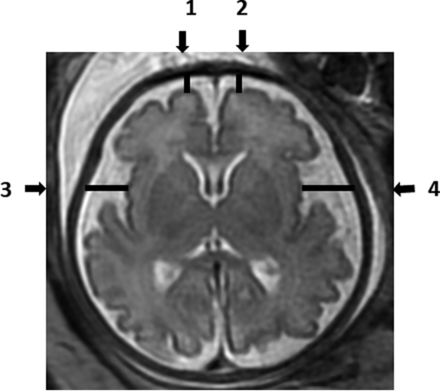

Each MR imaging examination was routinely read by 2 expert physicians to detect any abnormality. Measurements of the SAS size, which was identified by a high signal (white color) at T2-weighted imaging, were analyzed manually by a single reader (A.W.) on the PACS reading workstation. Measurements were recorded in 2D slices. The SAS was measured in millimeters, in 4 locations of the axial section (Fig 1), and in 6 locations of the coronal section (Fig 2). All measurements were obtained at the level of midinsula from the cortex to the internal margin of the cranium as shown in Figs 1 and 2: axial section - right frontal gyrus, left frontal gyrus, right insula gyrus, left insula gyrus; coronal section - right frontal gyrus, left frontal gyrus, right insula gyrus, left insula gyrus, right inferior temporal gyrus, and left inferior temporal gyrus.

Axial T2-weighted fetal brain image demonstrating the measurements of the subarachnoid space: 1) Right frontal gyrus. 2) Left frontal gyrus. 3) Right insula gyrus. 4) Left insula gyrus.